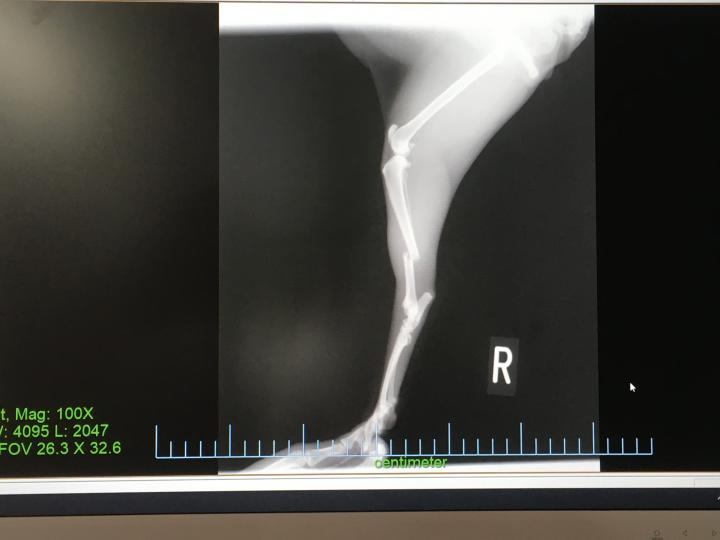

レントゲン画像を見たら、右足のスネに当たる部分がぽっきり

その上しっかりズレてる。

まって1mくらいの棚から落ちただけなのに。